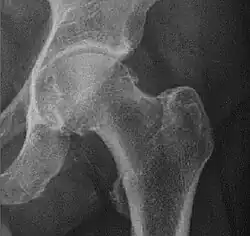

![Figure 5 (b). Coxa profunda.[3]](./_assets_/X-ray_of_coxa_profunda.jpg)